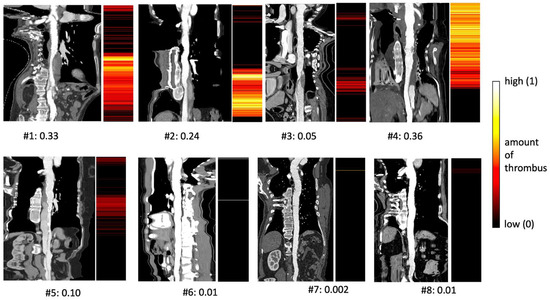

3.4. Calculation of Thrombus Score